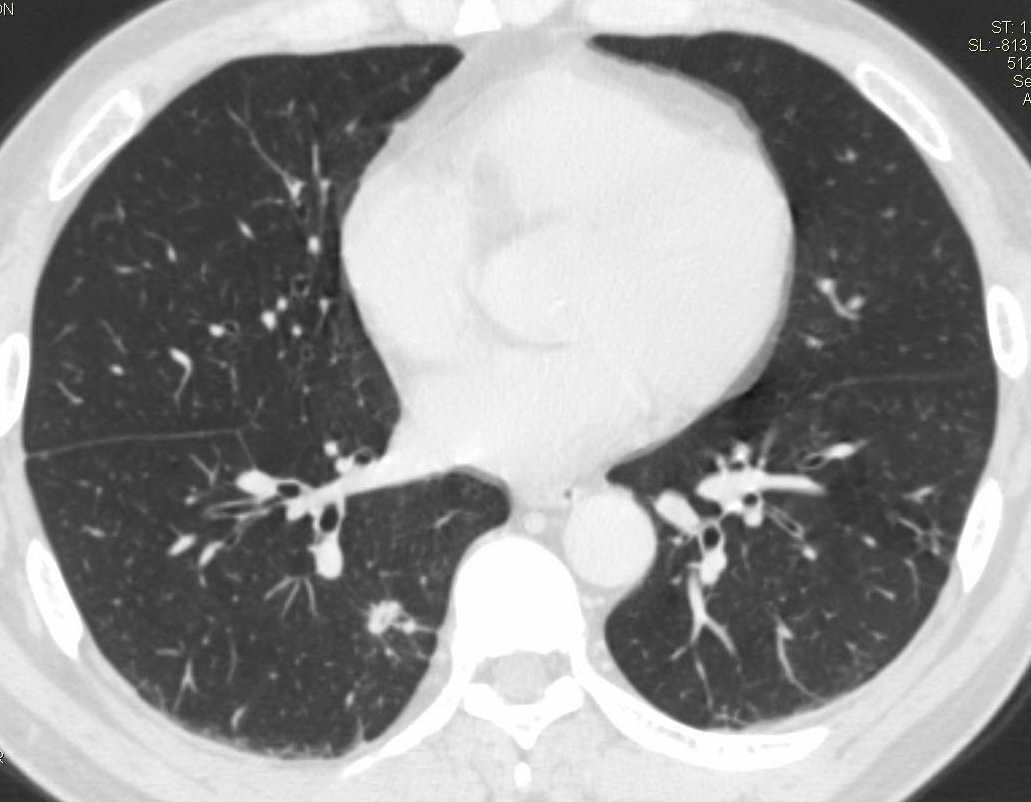

标题: CT15857:男性 58岁 咳痰带血 无发热 请各位大侠发表一下意见 [打印本页]

标题: CT15857:男性 58岁 咳痰带血 无发热 请各位大侠发表一下意见

两肺下叶肺纹理增多、增粗并呈“树芽状”改变。支气管扩张呈囊状,部分呈柱状改变。其周围可见散在的斑片样及条索样密度增高影,右肺下叶近叶间胸膜可见一形态不规则的高密度结节影,并与胸膜粘连。

考虑:支扩并发感染。

双肺多发炎性病灶,结核可能性大,建议抗炎治疗复查.右肺下叶前基底段结节灶,高度警惕肺癌可能

双肺间质性改变(间质纤维化?)伴支扩。右肺下叶有毛刺的小结节,考虑周围型肺癌可能性。